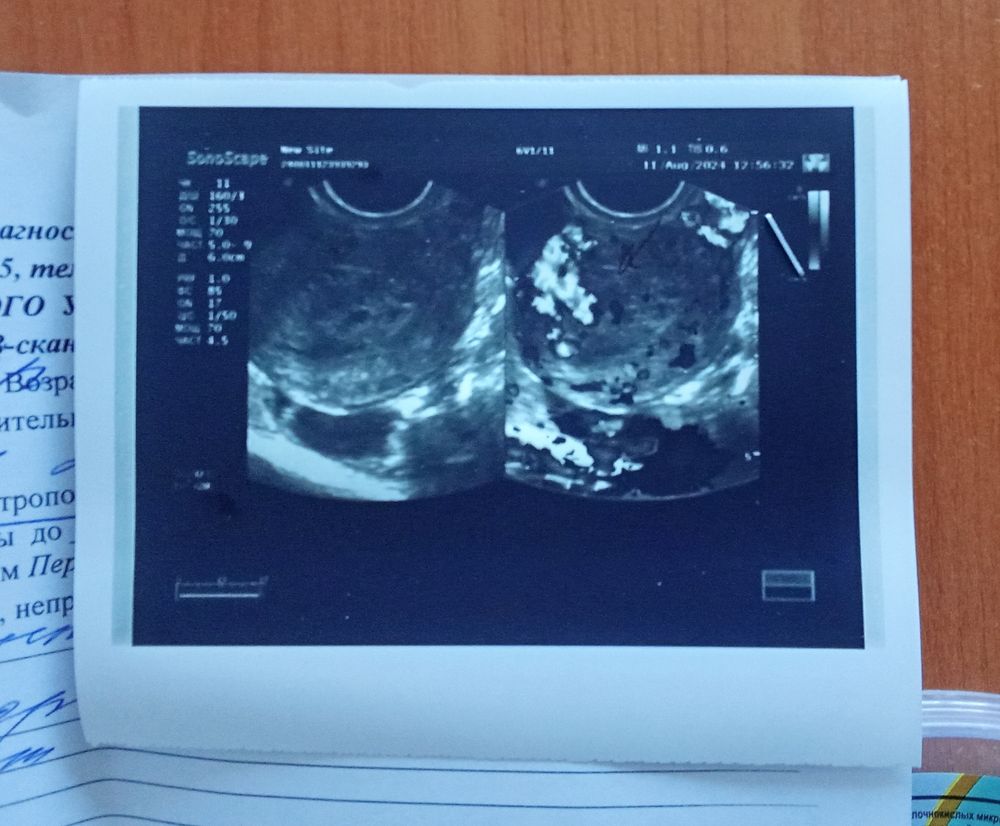

Ничего не понятно, когда у вас тесты полосатить начали, сколько задержка, какой срок. По узи у вас диагноз - гематометра, беременности нет. Есть сгусток крови и остаток плодных оболочек.

Вы не беременны, и у Вас по всей видимость был самопроизвольный выкидыш. В полости матки скапливается кровь и остатки хориона. Вам нужно оперативнее чем через две недели обратится к врачу

Анна Кутявина, у вас выкидыш был? Кровянистые выделения были или что? Вы не беременны. У вас гематометра. Норма это или нет зависит от того, когда начались выделения кровянистые. Хгч положительный потому что была беременность.

Анна Кутявина, и еще остатки хориальной ткани описали. Вам нужна вакуум-аспирация

Анна Кутявина, ну так кровь у вас в матке и остатки хориальной ткани.беременности тут нет . нужна чистка